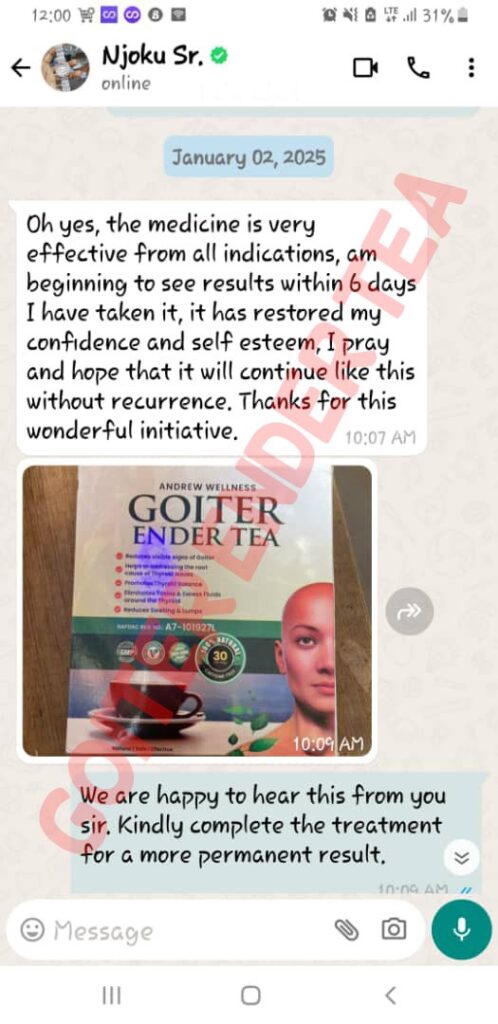

Goitre Ender Tea is the herbal product that thousands of Nigerians are using to cure all type of throat, mouth and neck problems.

FEW TESTIMONIALS FROM OUR CUSTOMERS

We have sold this product to a lot of people and many of them are calling back to tell us that it worked for them.